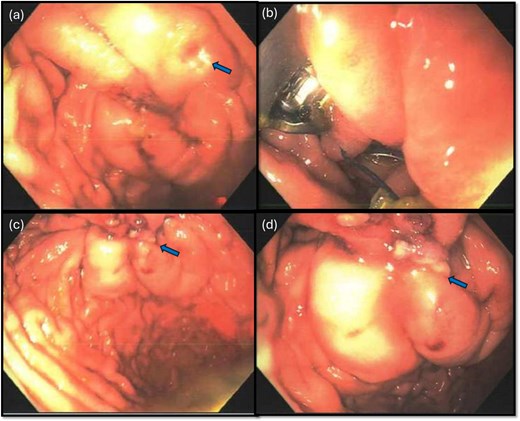

Endoscopic view of the perforation. The picture in (a) demonstrates the site of the perforation. The picture in (b) shows the use of the overstitch technique to perform the closure endoscopically. Pictures (c) and (d) demonstrate the area of perforation once the first and second layers of endoscopic closure are completed, respectively.

To aid endoscopic visualization of the small perforation, a Maryland grasper was gently inserted into it (Fig. 2); the grasper’s tip, visualized endoscopically, confirmed the exact location. The remainder of the esophagus, stomach, and duodenum appeared normal. The Overstitch™ endoscopic-suturing device, mounted on a double-channel therapeutic endoscope and utilizing a tissue-helix for full-thickness bites, was used. Three full-thickness inverted figure-of-eight 2–0 Prolene sutures were placed at the perforation. Laparoscopic visualization confirmed full-thickness suture placement before the sutures were cinched, effectively closing the gastric wall defect (Fig. 3).

A leak test was then performed by submerging the repair site under saline and endoscopically insufflating the stomach; no bubbling was noted, indicating a successful seal. The repair was reinforced with an omental patch, secured laparoscopically with a 2–0 silk suture (Fig. 4). A single drain was left in the abdomen, remaining fluid was suctioned. Endoscopic biopsies of the stomach and duodenum were obtained, and a nasogastric tube was placed.